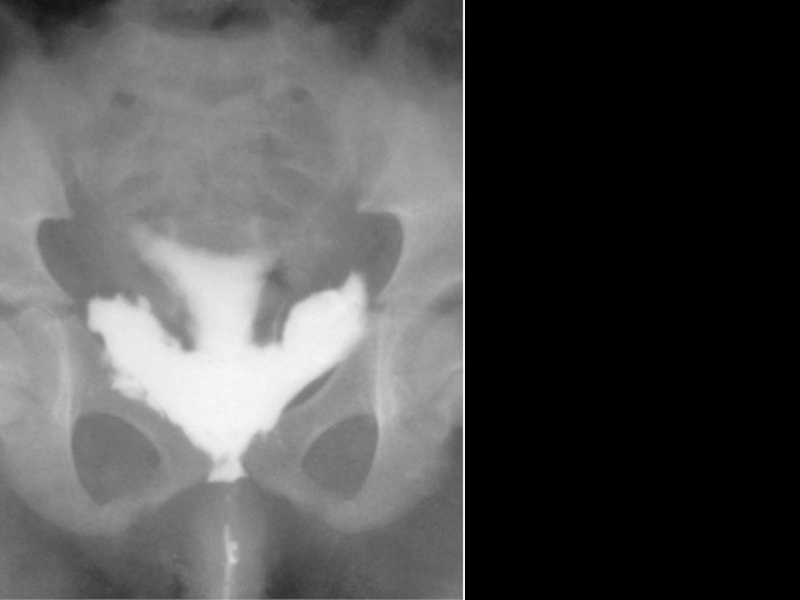

Слайд 33Ретроградная цистограмма. Внебрюшинный разрыв мочевого пузыря

Ретроградная цистограмма. Внебрюшинный разрыв мочевого пузыря